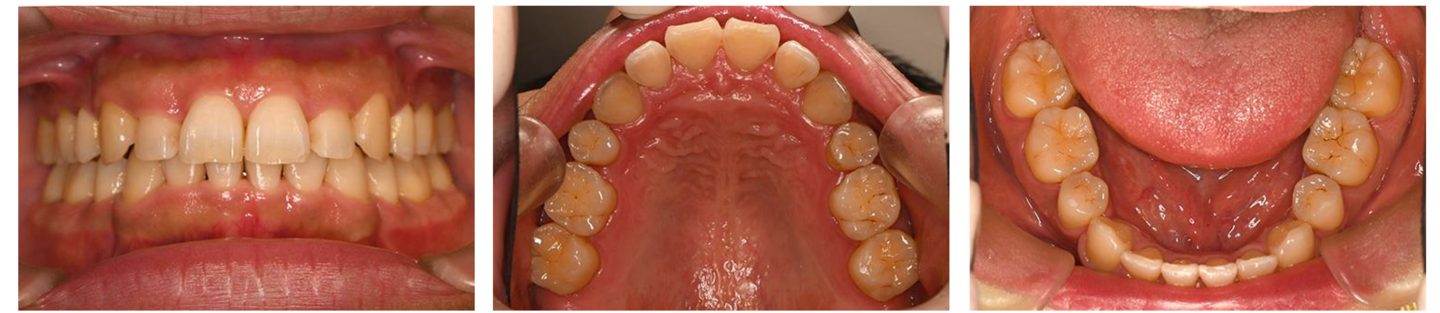

8歳女児 小児矯正にて1期治療終了 現在15歳で2期治療なし

治療前の写真

治療前 8歳

治療後 10歳

定期検診中

15歳

治療後の写真